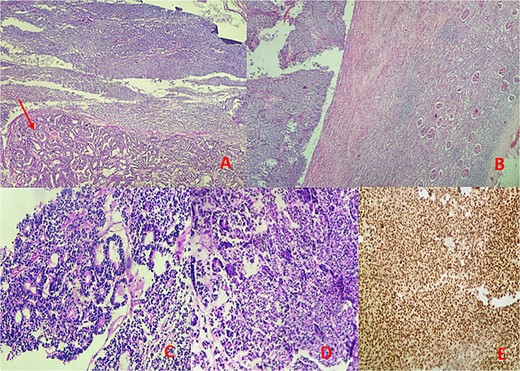

Microscopic examination identified a triphasic WT with mixed components: 60% blastemal, 35% epithelial, and a very focal mesenchymal component. The tumor was classified as stage II according to the National Wilms’ Tumor Study (NWTS) Group staging system. There was no evidence of anaplasia or nephrogenic rests. The tumor infiltrated the renal sinus without lymph node metastasis. Immunohistochemical staining revealed positive expression for cytokeratin, WT1, and cyclin D1, while CD10, CK7, and AMARC were negative (Fig. 3).

Microscopic findings: (A, B) hematoxylin–eosin (H&E) stain at low magnification reveals a mixed tumor with blastemal and epithelial components (arrow), showing well-defined borders pushing renal parenchyma. (C, D) Hematoxylin–eosin (H&E) stain at 40× magnification displays blastemal cells with scant cytoplasm, small size, mitotic activity, rounded overlapping nuclei, and primitive tubular structures. (E) Immunohistochemical analysis demonstrates diffuse nuclear staining for WT1.